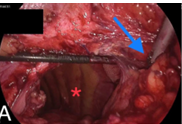

Congenital diaphragmatic hernia (CDH) is a birth defect involving improper formation of the diaphragm, leading to the protrusion of abdominal organs into the chest cavity. The CDH is classified depending on the location of the defect as postero-lateral, central and anterior. Depending on the side, it is classified as right, left and bilateral. A majority of CDH defects are postero-lateral defects and are commonly referred to as Bochdalek hernias (BH). Herein, the authors present the case of a 29 years old male patient diagnosed with a large left recurrent Bochdalek hernia. He was operated for it in another hospital by another surgeon 5 months back. That previous surgical intervention was initially planned via laparoscopy. But, intraoperatively, it had to be converted to open surgery due to technical difficulty. Post the first surgery, after about 1.5 months, he started developing pain in the back of his left chest. However, due to financial constraints, he did not seek any consultation with anyone at that time. The authors successfully performed a laparoscopic repair of this difficult condition. The rationale for reporting this case is to underscore the relative ease of a laparoscopic over open surgical intervention, on the ‘roof’ of the abdomen and also the lower chest. Also, it hopes to highlight that laparoscopic repair of BH is feasible even in challenging, difficult and recurrent scenarios, in an advanced setup backed up by the requisite surgical expertise.